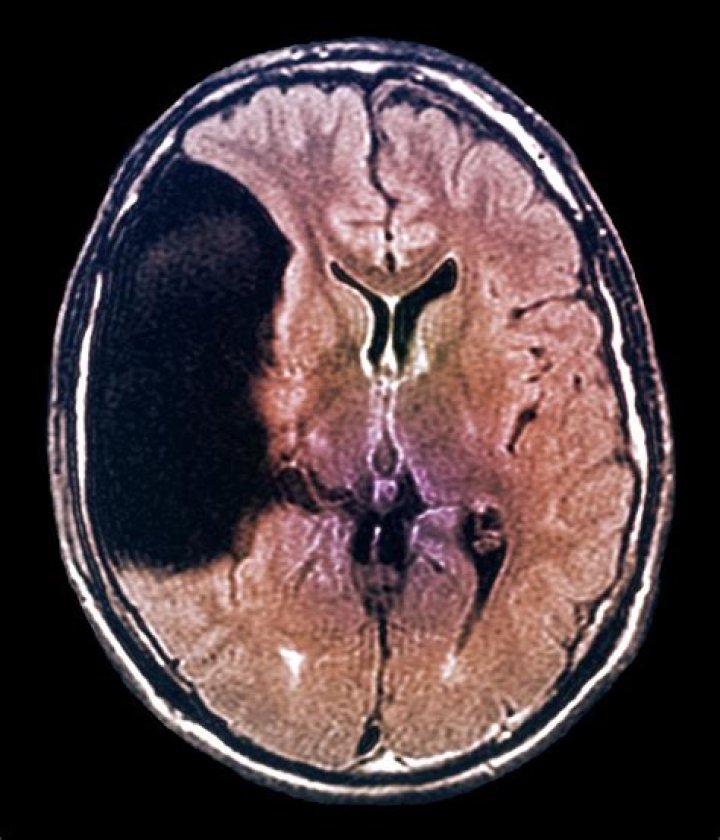

Can arachnoid cyst cause seizures

In many cases, arachnoid cysts do not cause symptoms (asymptomatic). In cases in which symptoms occur, headaches, seizures and abnormal accumulation of excessive cerebrospinal fluid in the brain (hydrocephalus) are common.

Treatment of Arachnoid Cysts The size of arachnoid cysts varies. The average arachnoid cyst size is less than 3 cm. An arachnoid cyst size of 3 cm or greater is considered dangerous.

Early detection and treatment of arachnoid cysts will help prevent symptoms from developing. If the cyst is allowed to grow, it may put pressure on the brain and spinal cord, leading to permanent neurological complications. Complications of untreated arachnoid cysts can be serious, even life threatening in some cases.